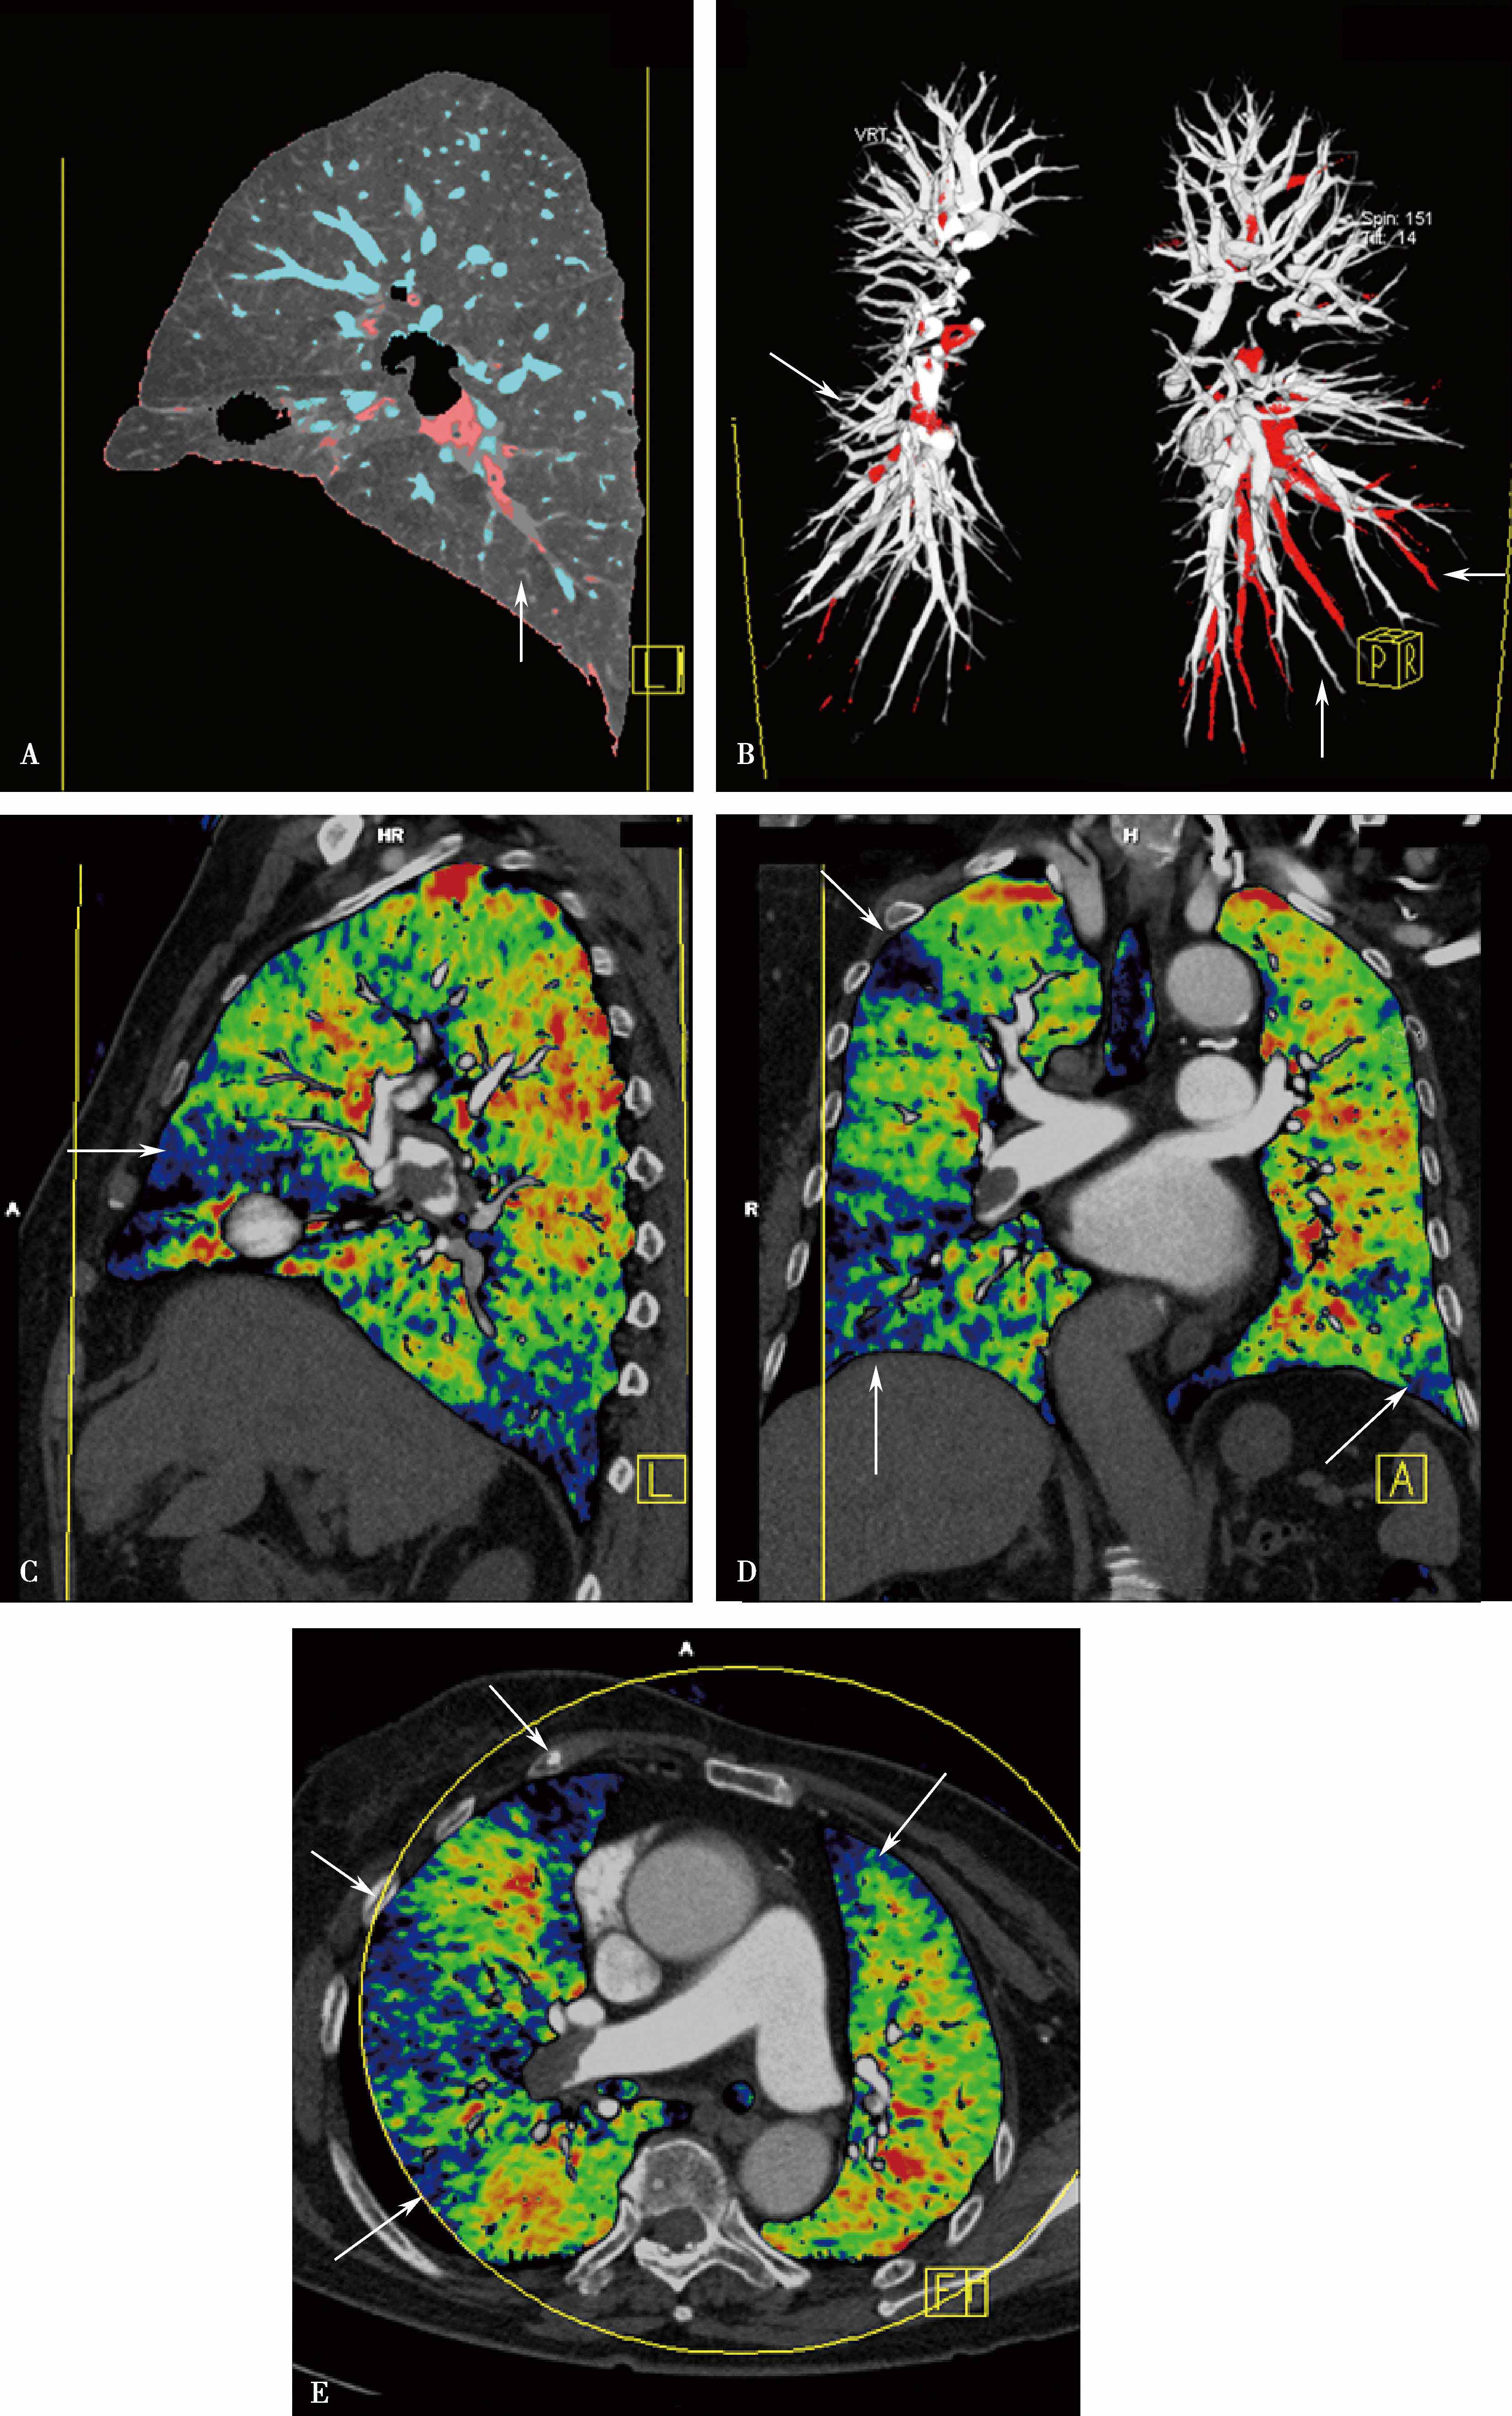

1.CT肺灌注成像肺血流灌注研究(EBCT资料,图8-3-1)足侧及背侧肺段正常灌注量:2.42ml/(min·ml)。 头侧及腹侧肺段正常灌注量:2.19ml/(min·ml)。容积扫描(解剖诊断)与功能扫描在肺段以上水平一致率为85%~100%。功能扫描提供肺血流定量研究,为诊断及治疗提供更多信息,指导治疗,评价治疗效果。

2.CT肺灌注成像肺栓塞的诊断应用 CTPA及肺部灌注成像可以显示肺动脉管腔形态,可以显示肺栓塞所引起的肺动脉形态学变化,同时提供栓塞后肺组织微循环改变,并以灌注伪彩图的形式直观地显示栓塞引起的灌注缺损区,为诊断及治疗提供更多信息,指导治疗,评价治疗效果。但CT肺灌注成像不能直接显示栓子的部位和大小,诊断应该结合CTPA所显示的肺动脉狭窄及梗阻,做出诊断。但是,研究表明灌注扫描对检出亚分段的栓塞,可以提高CTPA诊断敏感性(20%),有重要价值。与核素对照研究,高度相关( r =0.884)(图8-3-2~图8-3-6)。

图8-3-1 急性肺栓塞肺灌注成像(EBCT资料)

A、 B.治疗前, 灌注量0.15ml/(min·ml); C、 D.治疗后, 灌注量改善1.4ml/(min·ml)

图8-3-5 肺栓塞双能CT肺灌注成像(DELPI)

CTPA显示左肺舌叶段-亚分段、下叶内前基底段-亚分段未显影(A↑),灌注扫描示相应肺段灌注缺损(B↑),明确左肺舌叶段-亚分段、下叶内前基底段-亚分段肺栓塞诊断

图8-3-6 肺栓塞双能量CT能谱成像

A.右肺下叶外基底段栓塞(↑);B.能谱成像得到肺碘基物质图,梗阻肺段呈低灌注,清楚反映栓塞分布、程度(↑)